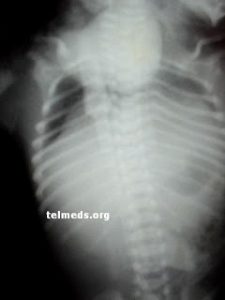

A queer and unusual case has put the doctors at National Institute of Cardiovascular Diseases (NICVD) in a difficult spot as a newborn was brought to the hospital with her heart located outside her tiny body. The case was brought to the hospital by National Institute of Child Health (NICH) as the hospital did not have doctors trained to handle such surgeries.

Due to the complications involved in the case, pediatric cardiologists and surgeons at NICVD refused to admit the baby who has been diagnosed with ectopia cordis-a condition in which the heart is located outside the body.

The baby girl diagnosed with ectopia cordis was born on Wednesday at a public hospital in Korangi. Seeing her condition, the doctors of the hospital transferred her to NICH where she was diagnosed.